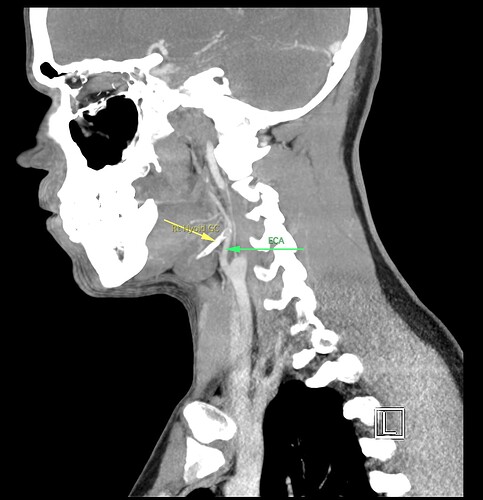

So, 2 years ago was the first time I came across Living with Eagle, filled with descriptions of all my symptoms, and a slew of scans showing very obvious bone chunks in the neck. Since I studied bio in college, and these bones are obvious, I figured I’d take a stab at looking at my own past scans and, low and behold, mild–but present–ossification of my stylohyoid ligament. Perhaps more relevant in my case, in the process of learning enough of the anatomy to understand axial images I noticed another weird thing–my right external carotid artery is in the wrong place. Instead of sitting lateral to my hyoid greater cornu, it’s medial. Hmm.

Tonsil surgery did solve the problem of my tonsils hurting, because they were gone, but no resolution of other symptoms. This was a year ago. I’ve been to PT, SLP, and now back to PT while I trial gabapentin for the neurologist. PT#2 discovered a bunch of significant atrophy in my upper right shoulder/back, and, you guessed it it’s all right sided. I’ve since then, thanks to radiopedia and Netter’s, also explored my images and noticed a few other anomalies in my scans, including an extended right thyroid superior cornu which appears to be pressing strongly into my neck also in the general area of pain, and an occipital artery branching off and wrapping around the internal carotid. Frustratingly these also weren’t mentioned on rads reports. My swallow study by the SLP showed obvious asymmetry with my swallow, but the SLP reported it symmetric and radiology apparently doesnt read the A/P view in their modified barium swallow studies? This is not inspiring faith in the academic institution I attended, but what can I possibly know they dont?